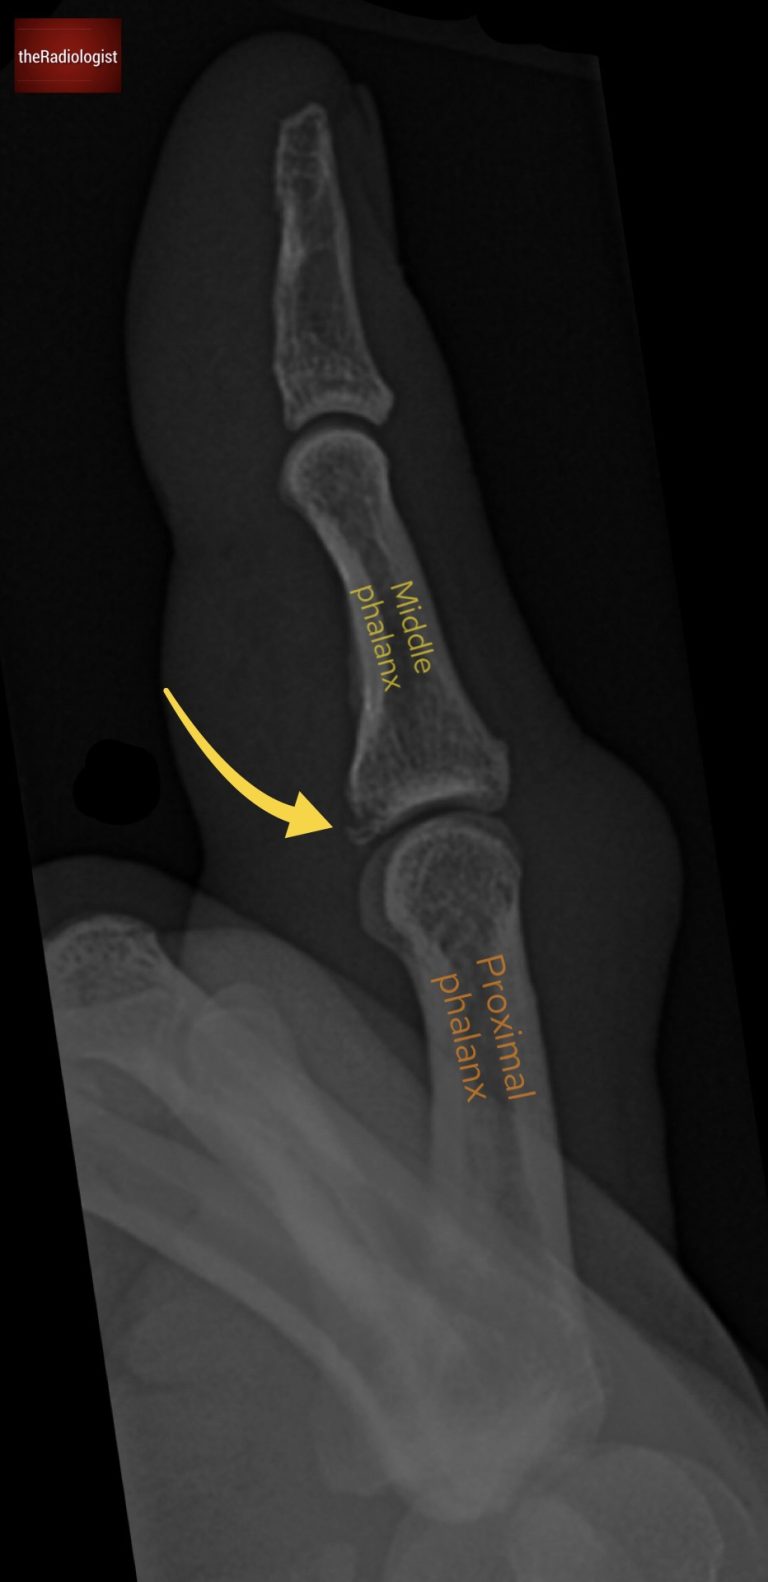

• Fracture Identification: This time, a break in the cortex is visible at the base of the middle phalanx, just above the proximal interphalangeal (PIP) joint.

This location is classic for a volar plate injury.

Lateral view shows a fracture at the base of the middle phalanx.

• Hyperextension can cause partial or complete rupture, often leading to an avulsion fracture at the middle phalanx base.

The injury may present with a visible avulsion fracture fragment. In severe cases, there can be subluxation or even dislocation of the PIP joint.